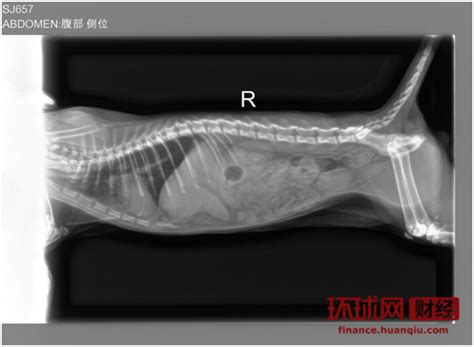

猫咪每次在猫砂盆内排泄都比较痛苦 , 它会觉得是猫砂盆对它造成了伤害 , 因此就不会在猫砂盆内上厕所了!然后在外面还是痛 , 因此不停的换地方!个人建议铲屎官观察猫咪每次排泄是否困难 , 排泄物中是否有血迹 , 排泄的量与以前相比是否有异常!如果符合以上任意一点 , 应及时就医!蓝短猫是否进入到了发情期!一般猫咪长到6个月左右的时候 , 就会进入到发情期了 。